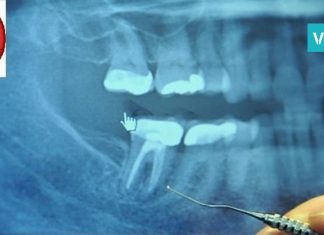

თანამედროვე სამყაროში ზურგისა და წელის ტკივილს „საუკუნის დაავადებას“ უწოდებენ. ამ პროცესში ჩართულია ხერხემლის სხვადასხვას სტრუქტურა: მალათაშუა დისკები, სახსრები, მყესები და კუნთები; ოსტეოქონდროზის დროს მალათაშუა დისკოს ნახეთქები უჩნდება. დატვირთვის დროს ამ ნახეთქებიდან შესაძლოა სითხემ გამოჟონოს. ამის შედეგად დისკოზე წარმოიშობა გამოზნექილობა, რომელსაც პროტრუზია ეწოდება. თუ ამ დროს დისკოს ბირთვიც გამოვარდა, მაშინ საქმე გვაქვს თიაქართან, რამაც შესაძლოა ზურგის ტვინის ფესვებისა და თვით ზურგის ტვინის დაზიანებამდე მიგვიყვანოს.